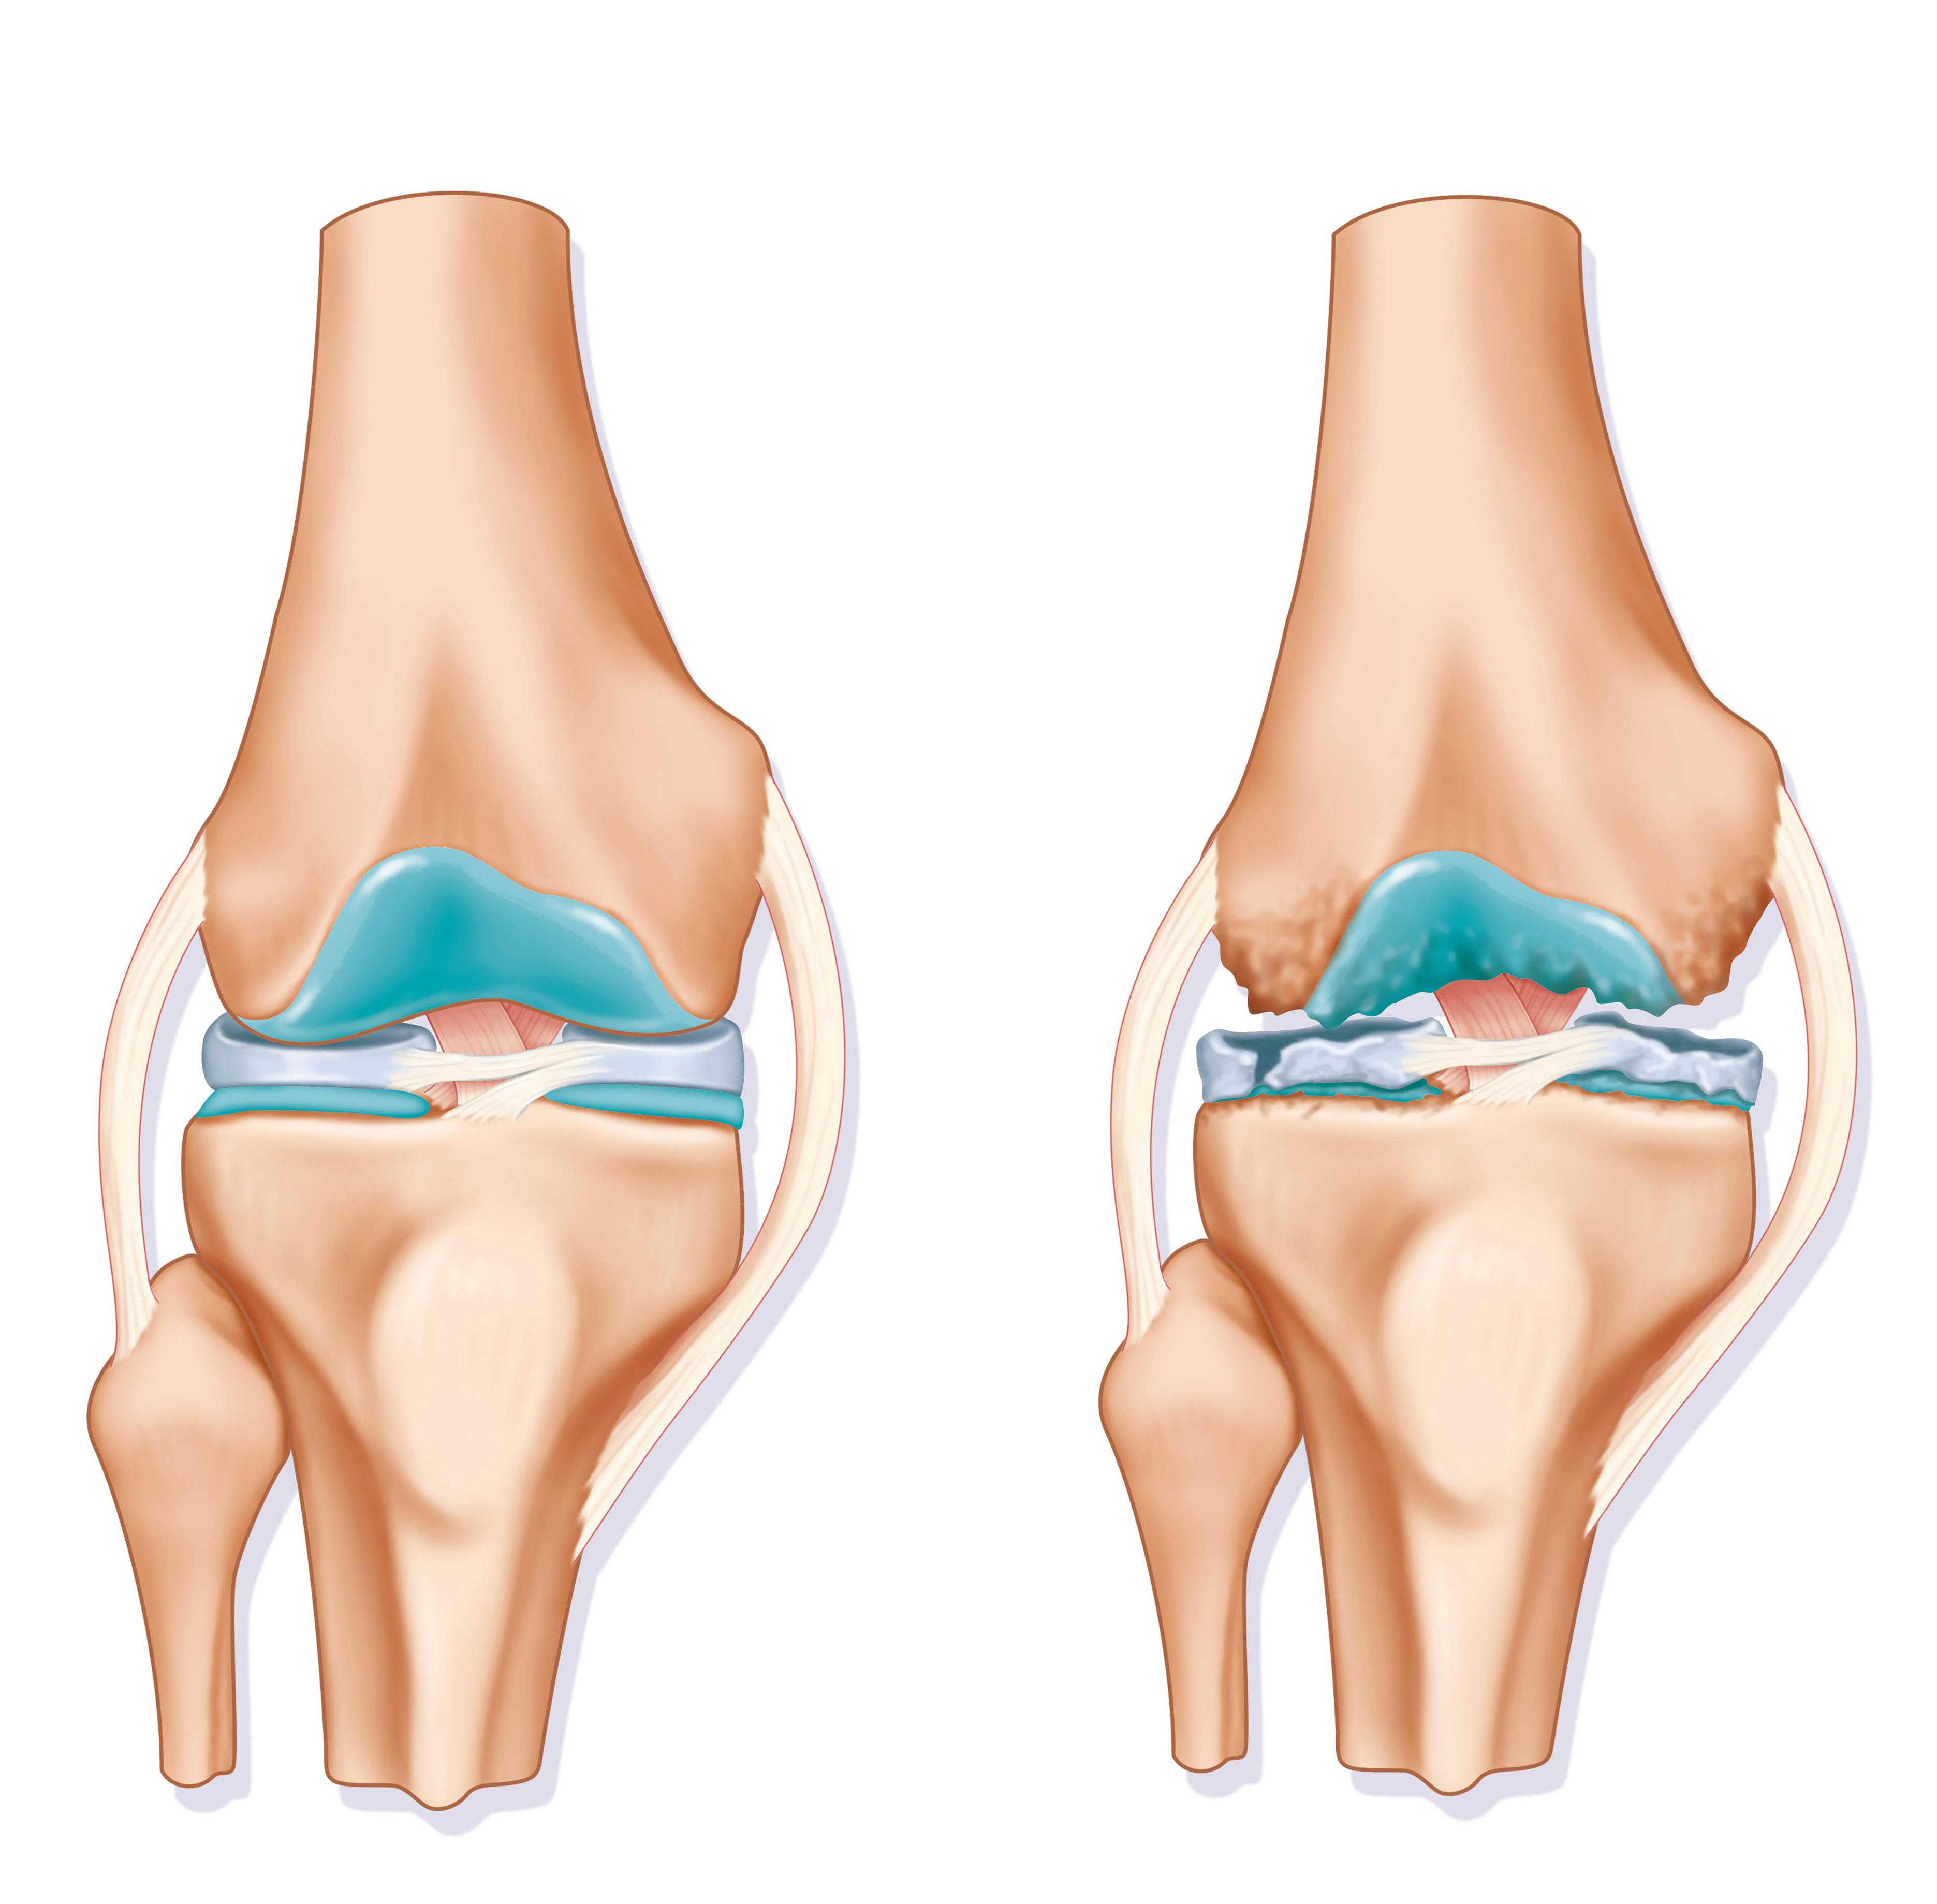

Osteoarthritis (OA) of the Knee

Osteoarthritis (OA) of the knee most commonly starts with damage to the articular cartilage, the meniscus, or both. This can occur through simple overloading of the joint by being overweight, from acute injuries to the knee, or from a combination of both. Having a family history of arthritis also increases the risk of developing OA. In the human knee joint, the medial compartment is the most likely to succumb to OA because it experiences the highest loads and, as a result, is also the most likely part of the knee to be injured.

Whereas other parts of our body heal back to their original state after an injury, articular cartilage and the meniscal cartilage do not. This means the damage to these structures can accumulate over time. The articular cartilage can become rougher and thinner, and the meniscus frayed and torn. This results in more friction and less cushioning between the ends of the bones and in the joint in general.

OA is not a complex disease to manage in its early years, but if these vicious cycles take hold and a patient’s overall health continues to decline, it can rapidly become part of a more complex condition. Eventually, all of the articular cartilage can be eroded from the ends of the bones. Some joint deformity, often with associated knee instability, can start to set in.